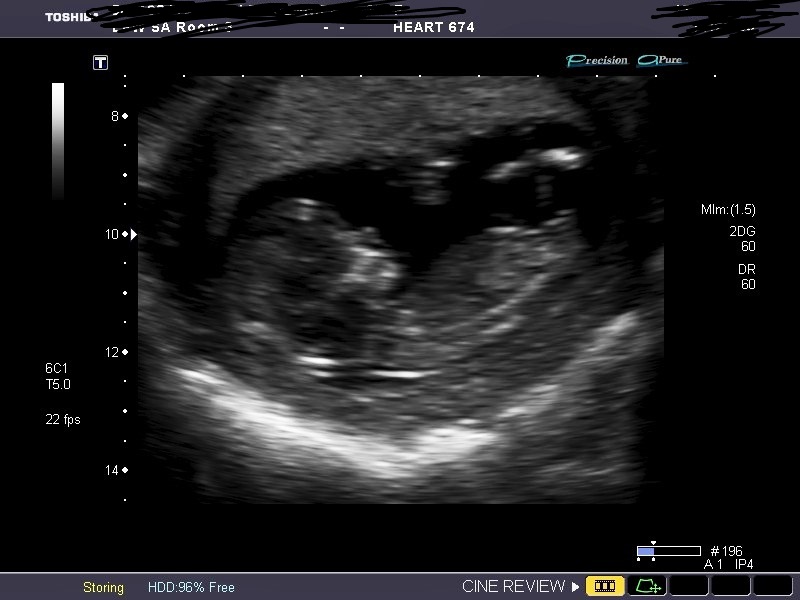

I think boy bc I see stacking, despite the relative flatness of the nub. It has time to rise, too.

stacking can be tricky on a photo! Always easier to see if the bump moves and is part of a cord or leg bone! This one must have been part of the cord bobbling around